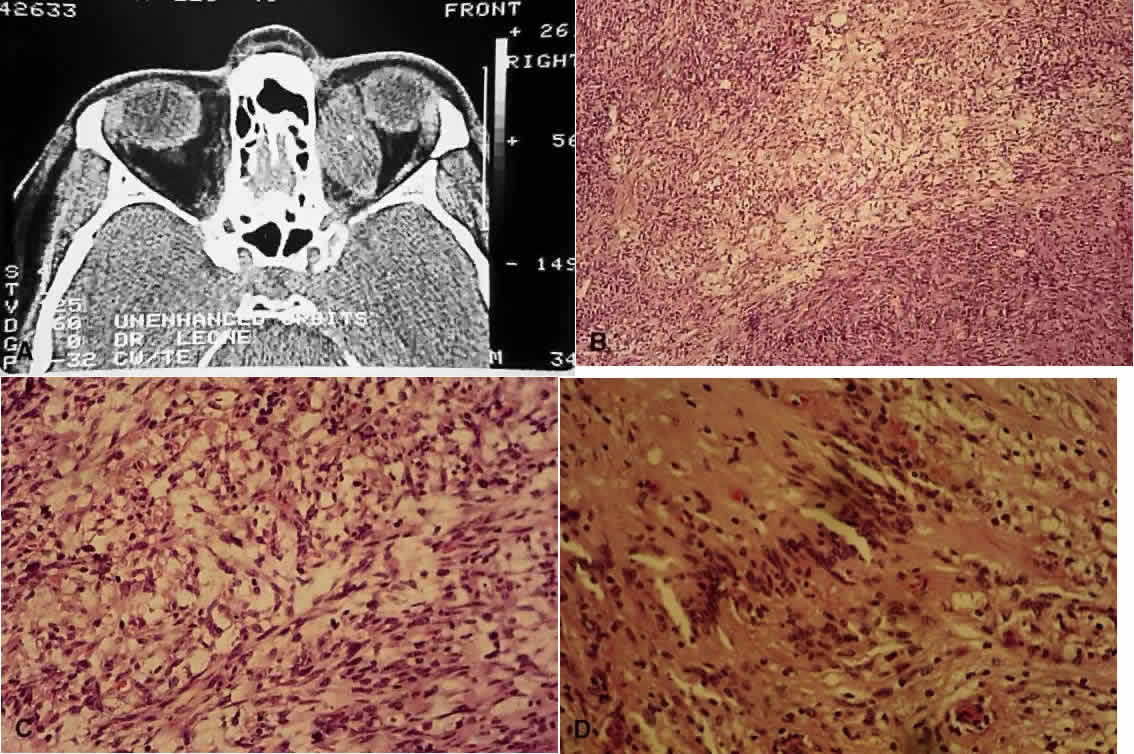

Fig. 7. Neurofibromatosis type 1. A. Clinical view of neurofibroma involving the right lids (H&E, × 7.8). B. Low-power view showing diffuse involvement of the dermis (H&E, × 31). C. Higher-power view shows infiltration and separation of striated muscle fibers (H&E, × 31). D. In another area are bundles of proliferated neural elements.

Schwannomas, or neurilemmomas, are proliferations of the Schwann cells that normally surround peripheral nerves. Histologically, two patterns can be evident—Antoni A, consisting of densely packed, swirling cells with indistinct cytoplasmic membranes, and Antoni B, which have a more mucoid appearance (Fig. 9). The eighth nerve tumors tend to cause deafness, so management of the cataracts becomes important to help preserve function. However, visual loss can also be caused by optic nerve and intracranial meningiomas.49 Retinal hamartomas occur in up to 22% of patients with NF2.39 In contrast, the occurrence of Lisch nodules and café-au-lait spots is unusual and not helpful in diagnosing NF2.48

Fig. 9. Neurilemmoma (schwannoma). A. Computed tomography scan of orbital neurilemmoma. B. Low-power view showing Antoni A (more densely packed cells) and Antoni B (more mucoid, paler areas) patterns (H&E, × 10). C. Higher-power view showing Antoni B pattern (H&E, × 25). D. High-power view of a Verocay body, where the long axes of the cell nuclei line up in register (H&E, × 31).